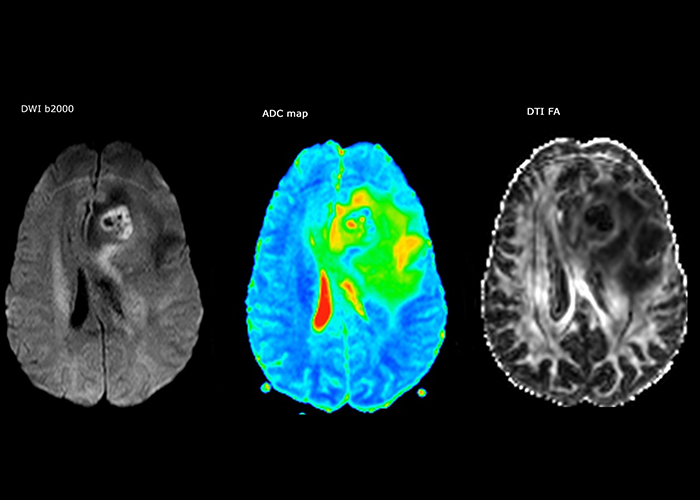

Dr. Savatovsky uses five or six different ExamCards for imaging a mass or a known tumor in the brain. “If there is a mass in the brain we try to characterize it to inform the neurologist for determining next steps or to help neurosurgeon prepare for a surgery or biopsy. For follow-up after treatment we have different protocols for different treatments and we adapt for intra- or extra-axial tumors.” “That is the most comprehensive exam we would do. Ingenia has the good spatial resolution and high SNR to provide all this information, and the flexibility to use shorter sequences, so we can do a very comprehensive examination in a limited time.”

“The biggest challenges are properly characterizing the lesion and giving the surgeon all the information needed, such as the location of vessels and functional areas. Sometimes a very comprehensive exam is necessary, such as when a mass has been discovered at another hospital after which the patient is referred to us. We then do both lesion characterization and preoperative imaging in one exam, so both morphologic and functional assessment. For morphologic assessment we will use pre- and post-contrast T1-weighted imaging, FLAIR to assess infiltration, and diffusion. For functional characterization we will perform perfusion, spectroscopy, and susceptibility weighted imaging to look for micro vessels or micro hemorrhage inside the lesion[4]. For preoperative imaging we perform specific morphologic imaging that is compatible with the navigation system; depending on the location of the tumor, we would do fMRI or DTI.”